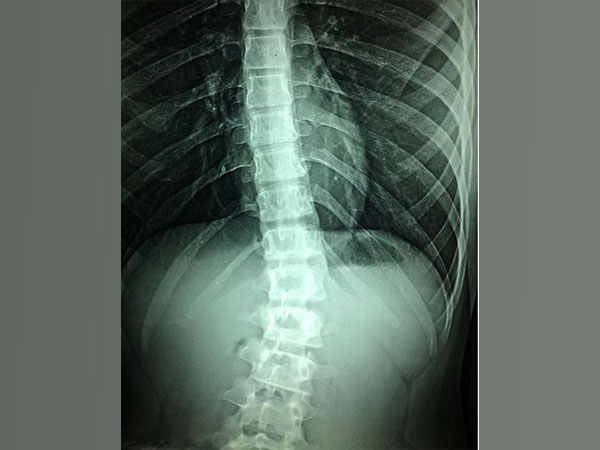

Researchers find epigenetic treatment can aid regrowth of sensory, motor neurons in spinal cord

Washington [US], September 21 (ANI): Currently, there are no effective treatments for spinal cord injury; physical...